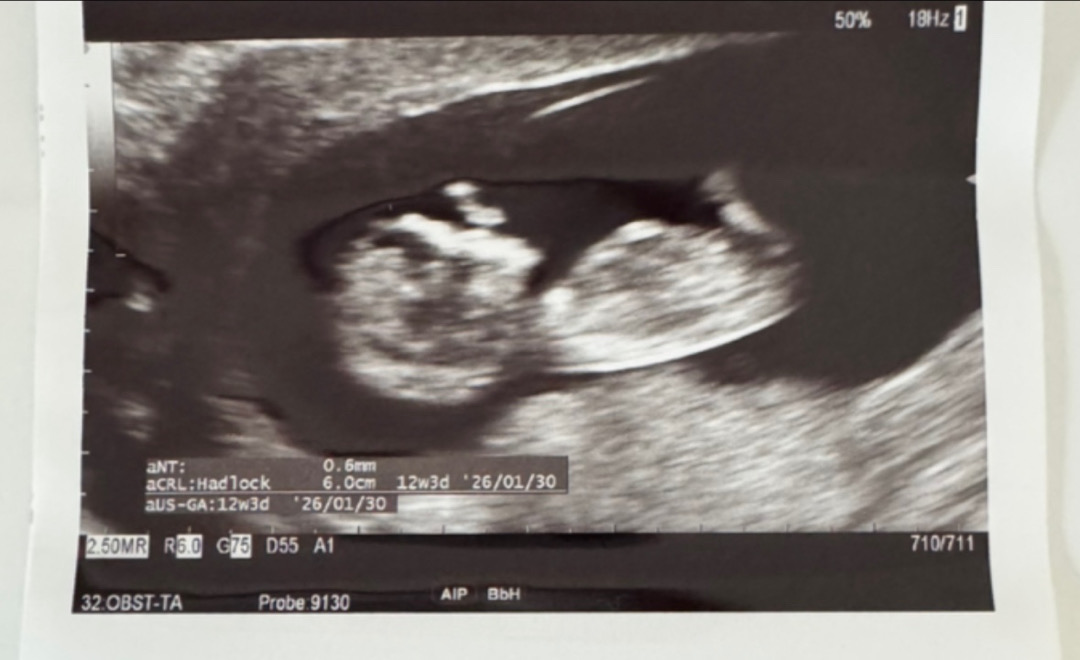

저도 각도법 한번 봐주세요 😅

요즘엔 각도법이 있다더라구요 ㅎㅎ 니프티검사해서 나오겠지만 .. 궁금해서요 ! 저는 하나도 모르겠어요 ㅠㅠ

딸인거같네용

사진에 생식기 부분이 안 나온 것 같아요🥺